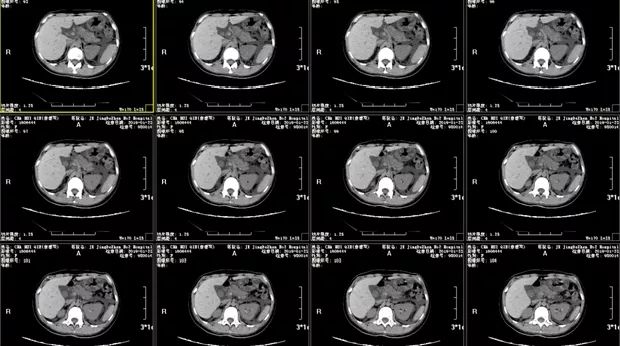

李元芳:患者入院时腹痛明显,首先完善了腹部CT检查(见下图),结果示:

1. 急性胰腺炎,大量腹水,请结合生化检查;

2. 腹膜后多发小淋巴结;

3. 左肾小结石;

4. 胃壁增厚水肿,考虑炎性病变,建议胃镜检查。

结合症状、体征及腹部CT检查,患者腹痛原因考虑为急性胰腺炎。但患者同时存在大量腹水,这让人疑窦丛生,单纯考虑炎性渗出未免太牵强,我看这其中定有隐情。

图一 腹部CT平扫图(部分)